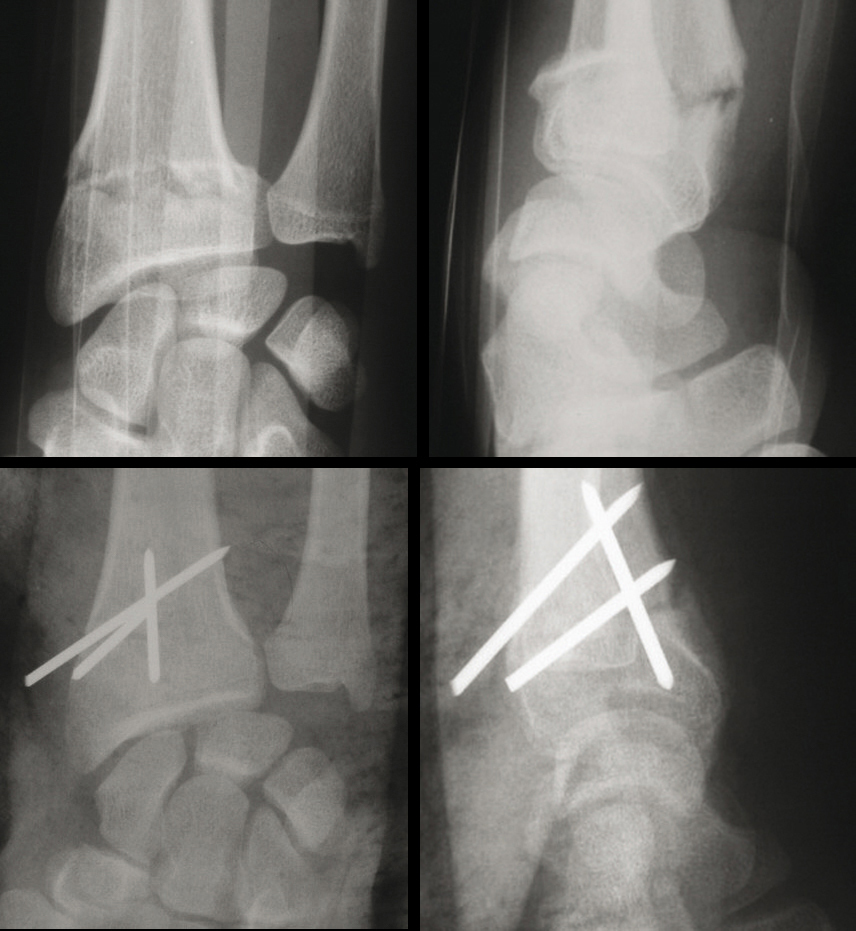

Fracture de Pouteau-Colles : fracture extra-articulaire à déplacement postérieur. (Haut, gauche) Radio de face. (Haut, droite) Radio de profil. Le traitement est parfois orthopédique mais le plus souvent réalisé par brochage percutané. (Bas, gauche) Radio de face. (Bas, droite) Radio de profil.